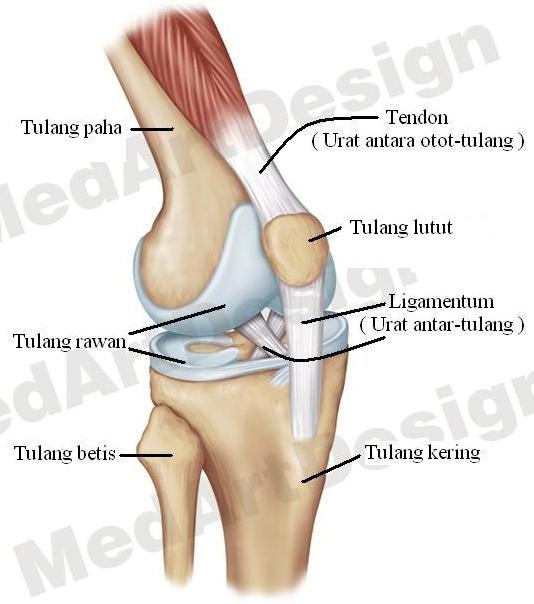

Bebas sakit sendi lutut | Harian Metro

Bebas sakit sendi lutut | Harian Metro

Bebas sakit sendi lutut | Harian Metro

Bebas sakit sendi lutut | Harian Metro

Bebas sakit sendi lutut | Harian Metro

Bebas sakit sendi lutut | Harian Metro